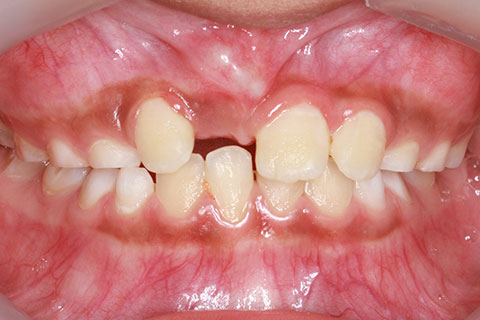

子供の乳歯が抜けて、かなりの時間が経つのに永久歯が生えてこないと心配して来院される親御様は多くいらっしゃいます。この場合、レントゲンにて確認すると大体の場合、もうしばらく待っていれば生えてくるであろうと予測がつきます。しかし、稀に歯の位置異常により、埋まったままの状態で生えてこないことがあります。この場合、待っていても生えてきませんので、矯正力により歯を引っ張り出す必要があります。これを矯正学では開窓・牽引術と呼び、歯肉を切開して、歯の表面を露出させ、そこに矯正器具を付けて、良好な位置まで引っ張り出すという治療法です。

開窓・牽引の症例